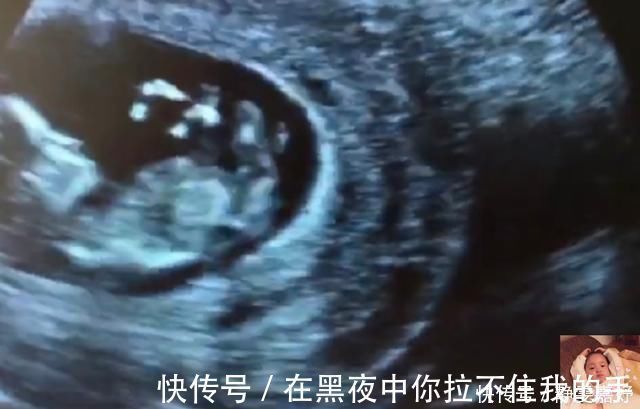

8)玩会脐带

孕妈肚子唯一陪伴胎宝宝就是脐带了,所以调皮的胎宝宝就会拿着脐带自己在那玩,但有些胎宝宝太贪玩,不小心给自己锁了喉,弄成了脐带绕颈。